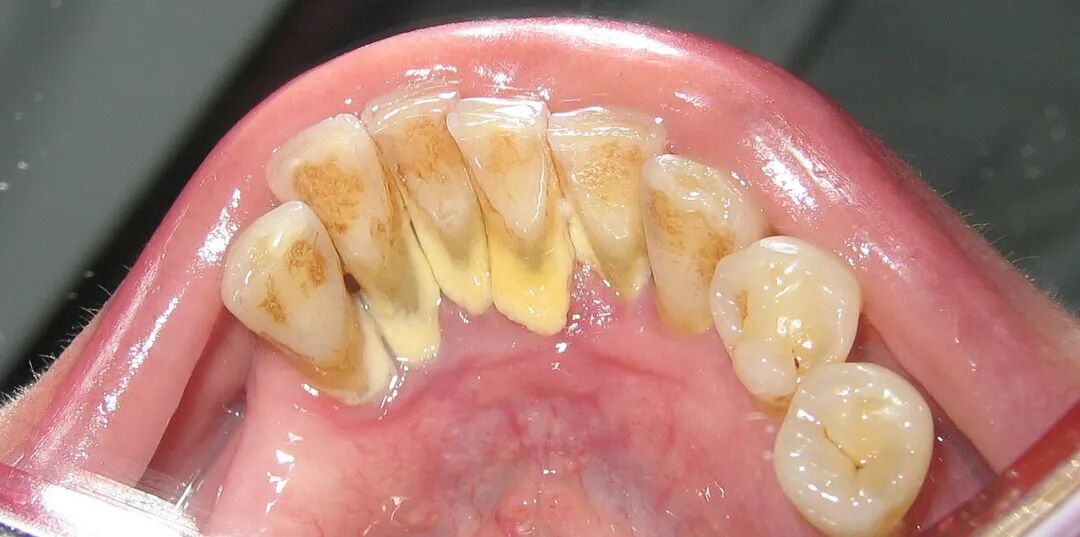

这也解释了为什么牙结石最容易出现在下门牙内侧、上后牙的外侧,这些位置都是唾液腺开口处,矿物质源源不断供应,堪称牙结石的“高产区”。

牙结石的表面粗糙、多孔,像极了细菌的“豪华酒店”。它会吸附食物残渣、让细菌积聚,让这些细菌分解蛋白质、释放出臭鸡蛋气味的硫化物——也就是所谓的“口臭”。